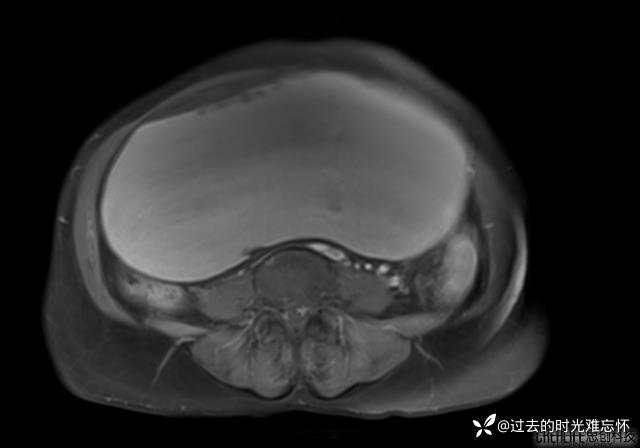

患者性别:女

患者年龄:65岁

主诉: 发现腹部隆起半年余。无其他明显不适。

浆液性囊腺瘤 (22)